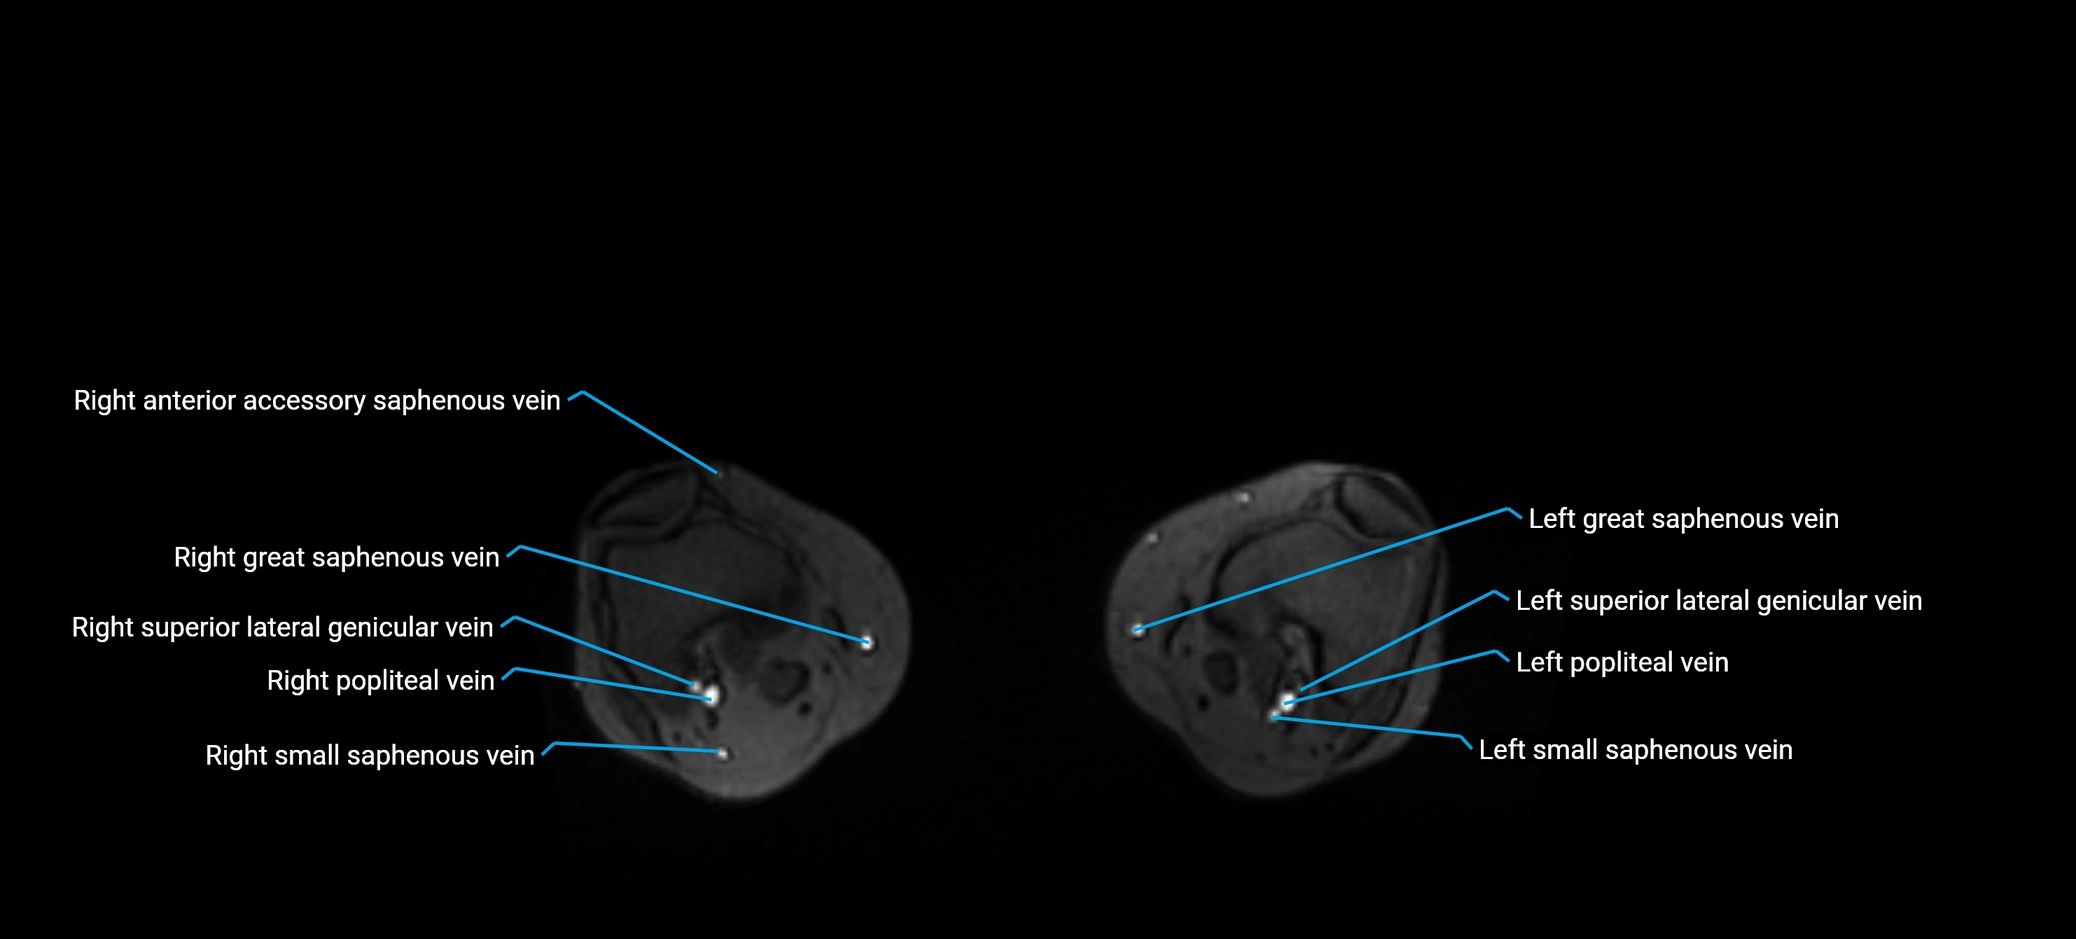

MRI image

image